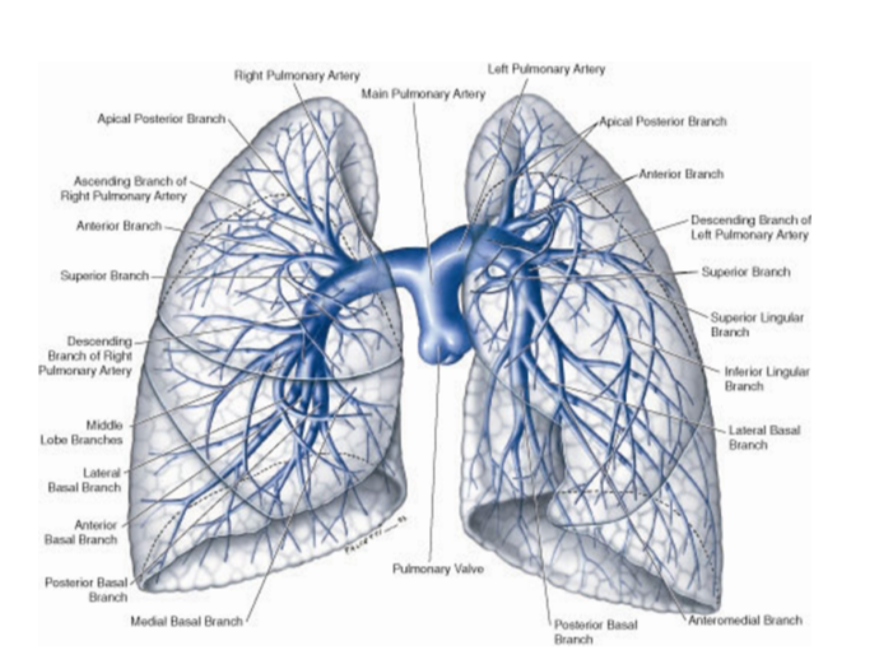

Overall vasculature of the lungs image

Pulmonary arteries (overall)

1 right, 1 left, originate from the pulmonary trunk & carry deoxygenated blood to the lungs from the right ventricle of the heart

Bifurcation of pulmonary trunk occurs to left of midline just inferior to vertebral level TIV/V, and anteroinferiorly to the left of the bifurcation of the trachea

Right vs left pulmonary arteries

Right pulmonary artery —

Slightly longer than left

Crosses horizontally at the mediastinum passes anteriorly & inferiorly to the bifurcation of the trachea, & anteriorly to the right main bronchus — also posteriorly to the ascending aorta, superior vena cava, and upper right pulmonary vein

Enters into root of lung giving off a large branch to the superior lobe of the lung

Main branch continues through hilum to give off a second recurrent branch to superior lobe before dividing to supply both the midline & inferior lobes

Left pulmonary artery —

Shorter than the right, anterior to the descending aorta & posterior to the superior pulmonary vein

Pulmonary veins —

On both sides — superior & inferior pulmonary vein

Carry oxygenated blood from lungs back to heart

Begin at hilum, pass through root of lung, & immediately drain into left atrium

Bronchial arteries

Along. with the veins form part of the nutritive system of vasculature of the lungs

Interconnect within the lung with branches of the pulmonary arteries & veins

Originate from the thoracic aorta or one of its branches —

A singular right bronchial artery normally arises from the third posterior intercostal artery

Occasionally originates from upper left bronchial artery

2 left bronchial arteries directly arise from the anterior surface of the thoracic aorta —

Superior left bronchial artery arises — vertebral level TV

Inferior left bronchial artery arises inferior to left bronchus

They run on the posterior surfaces of the bronchi & ramify in the lungs to supply pulmonary tissues